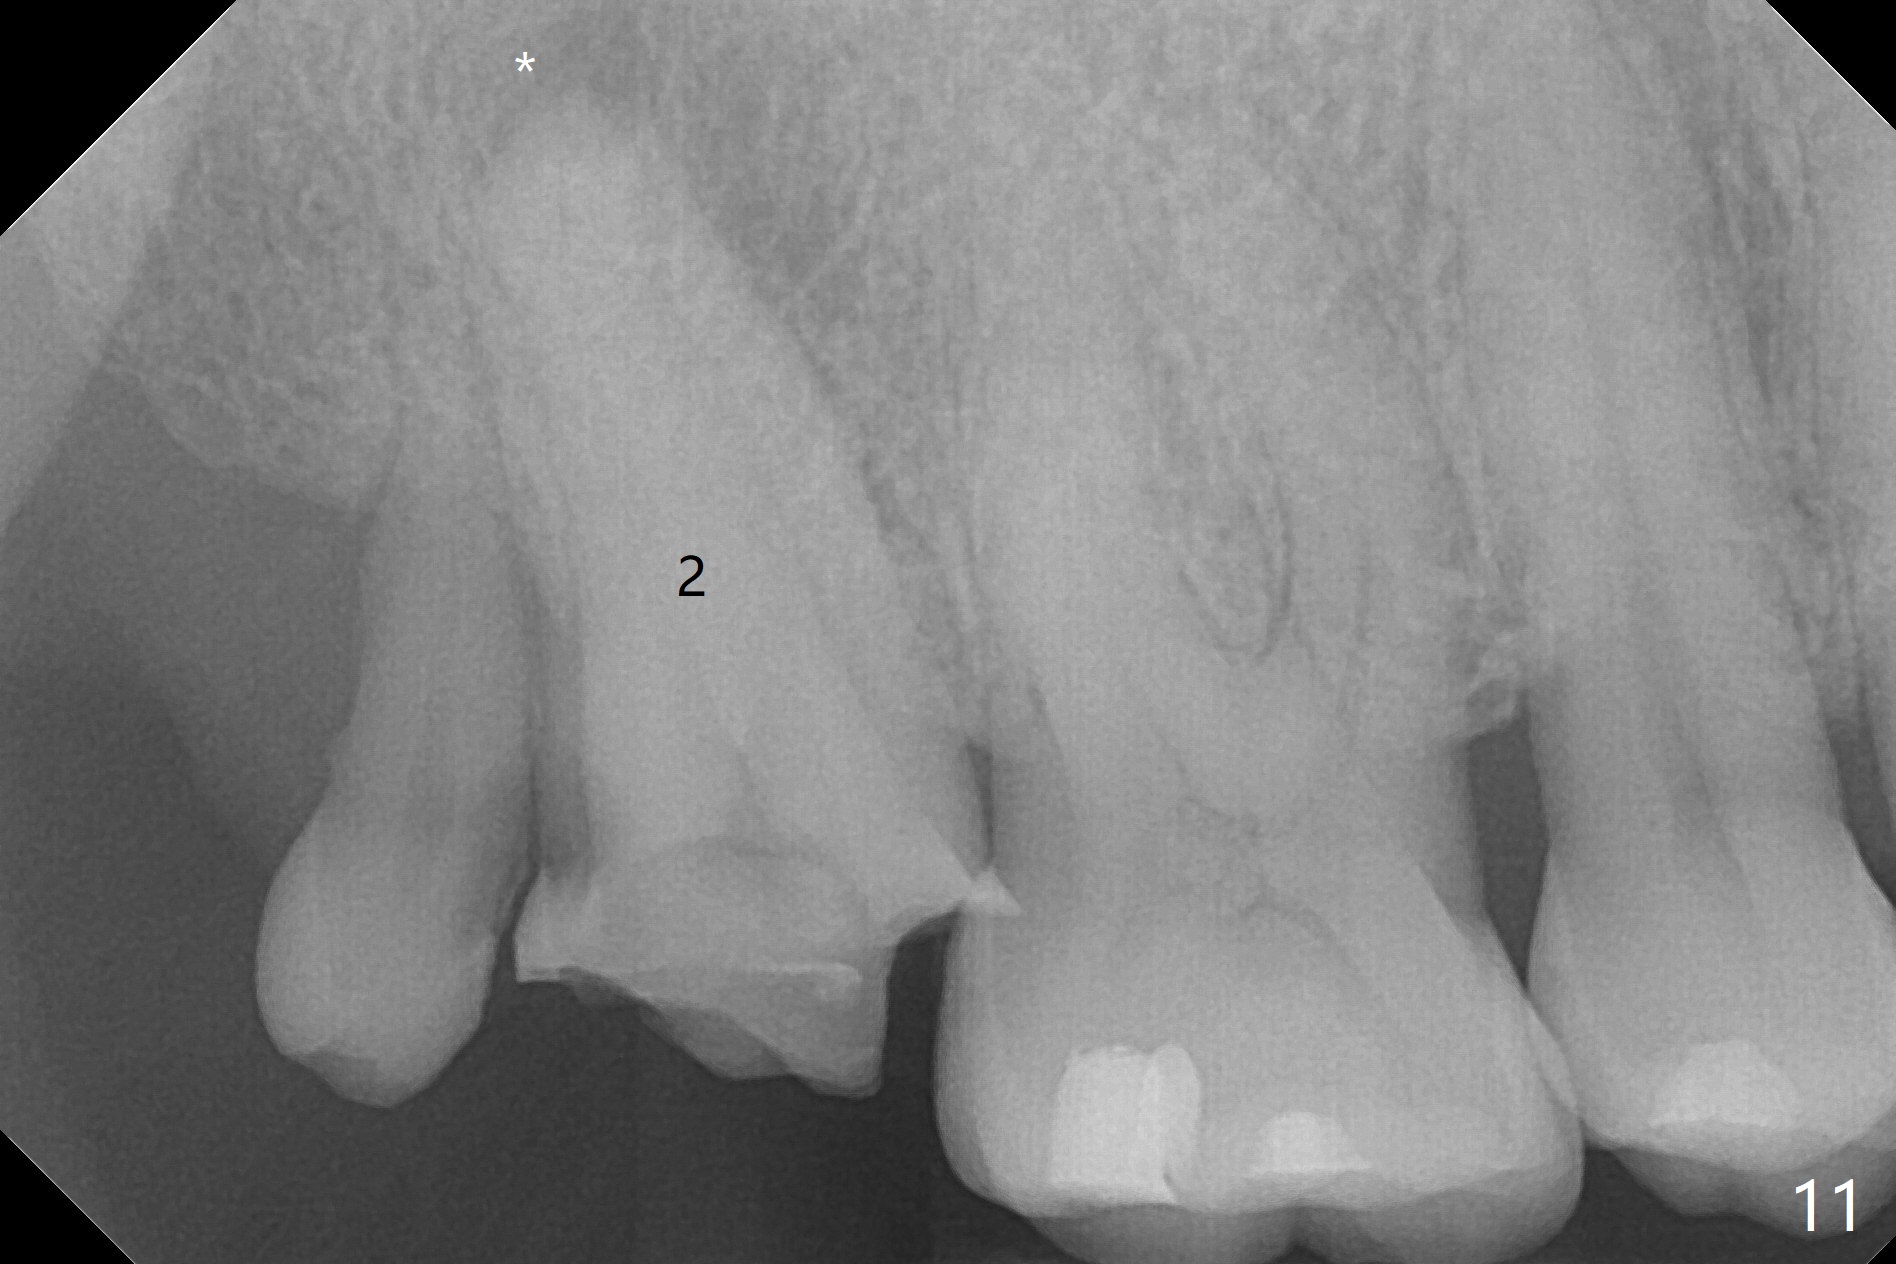

When the residual roots of the tooth #30 (Fig.1) are removed, the buccal crest is found ~ 2 mm apical to the lingual one (Fig.2 <); while the initial depth of osteotomy is 11.5 mm (yellow lines), the parallel pin is 10 mm long. To place a 5x11.5 mm implant at the level of the buccal crest (Fig.4 (>45 Ncm)), subsequent osteotomy depth is 13 mm using the lingual crest as a landmark (Fig.3 (4 mm drill in place)). After insertion of a 5.7x5.5(3) mm abutment, Vanilla Graft is placed (Fig.5 * with 2 mm buccal gap). The abutment with a provisional is loose 4 months postop (Fig.6). The permanent restoration is cemented 6 months postop. The abutment screw is loose and fractured 8 and 11 months post cementation, respectively (Fig.7). The fractured screw seems to be loose within the implant well and is easily re-winded out using Screw Removal Kit (sr-kit.html). When the crown/abutment at #30 is loose 2nd time 1 year 7 months post cementation (Fig.8 taken post retightening), the screw at #19 fractures. The tooth #2 needs a crown. The patient cannot use the anterior teeth, since the teeth #8 and 9 have root fracture. Can extraction and bone graft increase bone height? The screw re-fractures 9 months later (Fig.9). The dislodged crown is sectioned; the abutment is reseated completely (Fig.10) for a new crown. The tooth #2 needs RCT, B-U and crown, while the tooth #1 extraction (Fig.11).